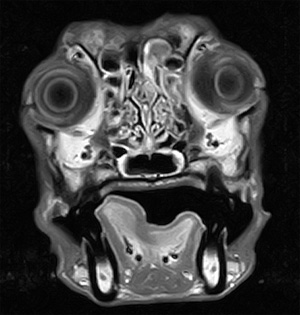

5~6歳以上の去勢手術をしていないオス犬に多い病気ですが、メス犬や去勢した犬に起こることもあります。お尻の筋肉が萎縮した結果、筋肉の隙間から直腸や膀胱が皮膚の下にとびでてしまいます。これにより便が出にくくなったり膀胱炎になったりします。手術をすることで機能回復および今後の致死的な状況を回避することができます。当院では去勢手術→結腸固定→前立腺固定→骨盤隔膜構成筋の縫縮→内閉鎖筋フラップ→浅臀筋フラップの順で通常腹側・臀部左右両側同時に行います。また老化以外に、筋肉が萎縮する原因があったり、腹圧がかかる原因があったりする場合も多いので、再発防止のためそれらの診断・治療も重要です。今回のワンちゃんも無事手術も終わり元気に退院しました。よかったね。